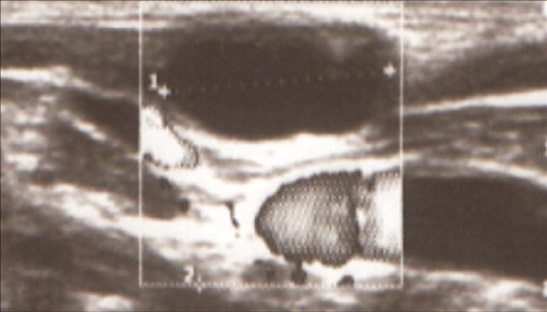

Con la sospecha de quiste branquial, se remitió a Cirugía Pediátrica, dónde se volvió a solicitar una ecografía cervical en Radiología, confirmándose la presencia de dicha lesión quística (8,3 × 10 × 18 mm, ejes AP × T × CC) en el espesor del esternocleidomastoideo derecho, que podría corresponder a un quiste del segundo arco branquial atípico, sin poder descartar malformación vascular de bajo flujo tipo línfática macroquística unilocular (Fig. 2). En el momento actual, la paciente está pendiente de completar el estudio para filiar el tipo de malformación congénita cervical.

| Figura 2. Ecografía Doppler |